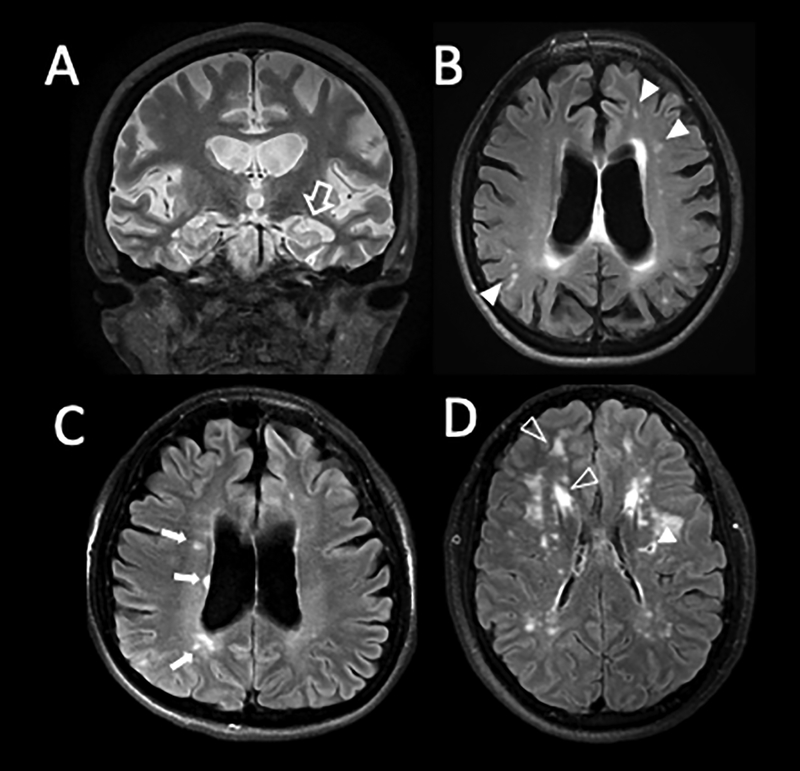

In the clinic, Magnetic Resonance Imaging (MRI) of the brain provides detailed in-vivo imaging of the progressive changes associated with neurological disorders, cognitive decline and dementia. This technology shows brain volume loss as the ultimate outcome of seemingly different pathophysiological processes (Figure 1:A–D). To date MRI remains the most effective form for diagnosis and non-invasive tool to assess disease progression, but it does not identify causation and it is unable to pint-point molecular mechanisms for the disease.

Figure 1: Magnetic Resonance Imaging (MRI) as a tool to diagnose neuronal disease.

A: Coronal T2 weighted image of 55-year-old woman with substantial hippocampal atrophy (open arrow) and volume loss consistent with Alzheimer’s disease. B: Axial FLAIR T2 image of the same patient illustrating coexisting microvascular ischemic changes (filled arrow heads). C: Axial FLAIR T2 in a 32-year-old patient with Advanced Multiple Sclerosis (MS). Note the orientation of the white matter lesions nearly touching ventricular surface (small arrows). This patient too has volume loss as indicated by her enlarged ventricular system and cortical atrophy. D: FLAIR T2 images in a young CADASIL patient with minimal deficits. Filled arrow head shows gliosis around a prior small lacunar stroke. Open arrow heads show prominent multifocal areas of white matter hyperintensity typical for CADASIL.

The most common form of monogenic hereditary vasculopathy associated with dementia is: cerebral autosomal dominant arteriopathy with subcortical infarcts and leukoencephalopathy (CADASIL) [4*]. Patients with this disease often become symptomatic in the second to fourth decade of life with complex migraine phenomena and strokes. Because of the brain MRI appearance (Figure 1) and their relative young age, patients with CADASIL are often misdiagnosed as suffering Multiple Sclerosis (MS).